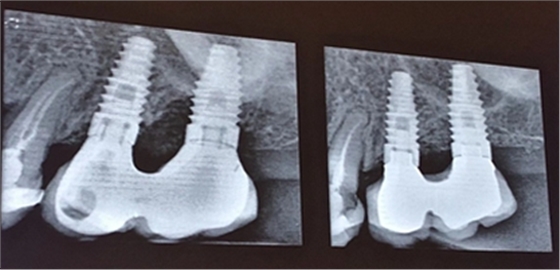

4、種植體周圍炎的治療

接下來Dr. Laurence Adriaens介紹了種植體周圍炎的治療,即非手術(shù)方式治療和手術(shù)方式治療。非手術(shù)方式治療提倡對患者進行有效的口腔衛(wèi)生指導(dǎo),患者必須掌握有效的菌斑控制方法,以保持良好的口腔衛(wèi)生,還可以選用種植體專用的牙線清潔義齒鄰面及其周圍軟組織。同時應(yīng)養(yǎng)成每半年到一年定期復(fù)查,進行專業(yè)清潔的習(xí)慣。

手術(shù)方式治療則需通過翻瓣清潔種植體及修復(fù)體上菌斑牙石,推薦在此過程中使用士卓曼鈦刷,因為該鈦刷不會損傷種植體表面細微結(jié)構(gòu)。之后進行植骨蓋膜來促進種植體周圍吸收部分的骨的重建。